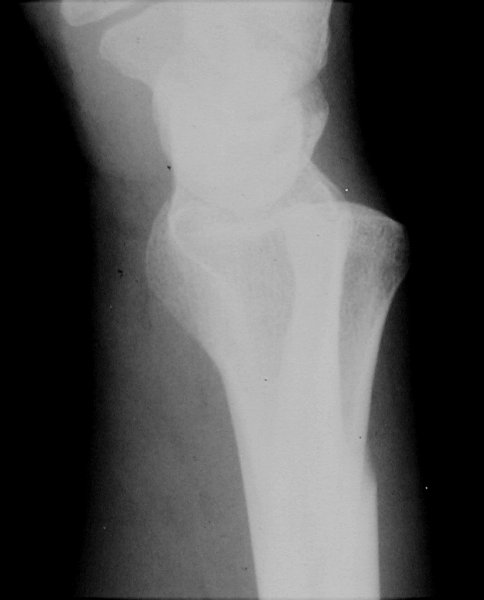

Return to Galeazzi's Fracture